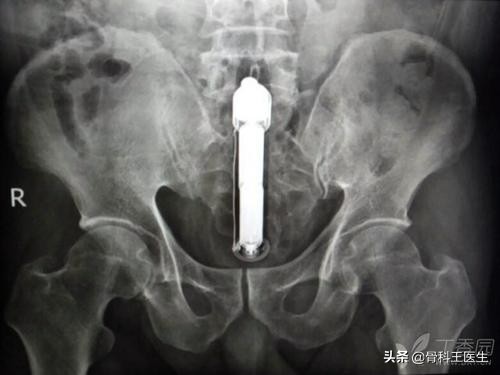

4、肛门、结直肠取异物:

说到从肛门进去,那我们取的东西就太多了,这地方太能装了。

不认识就不发了,我们发一些认识的: